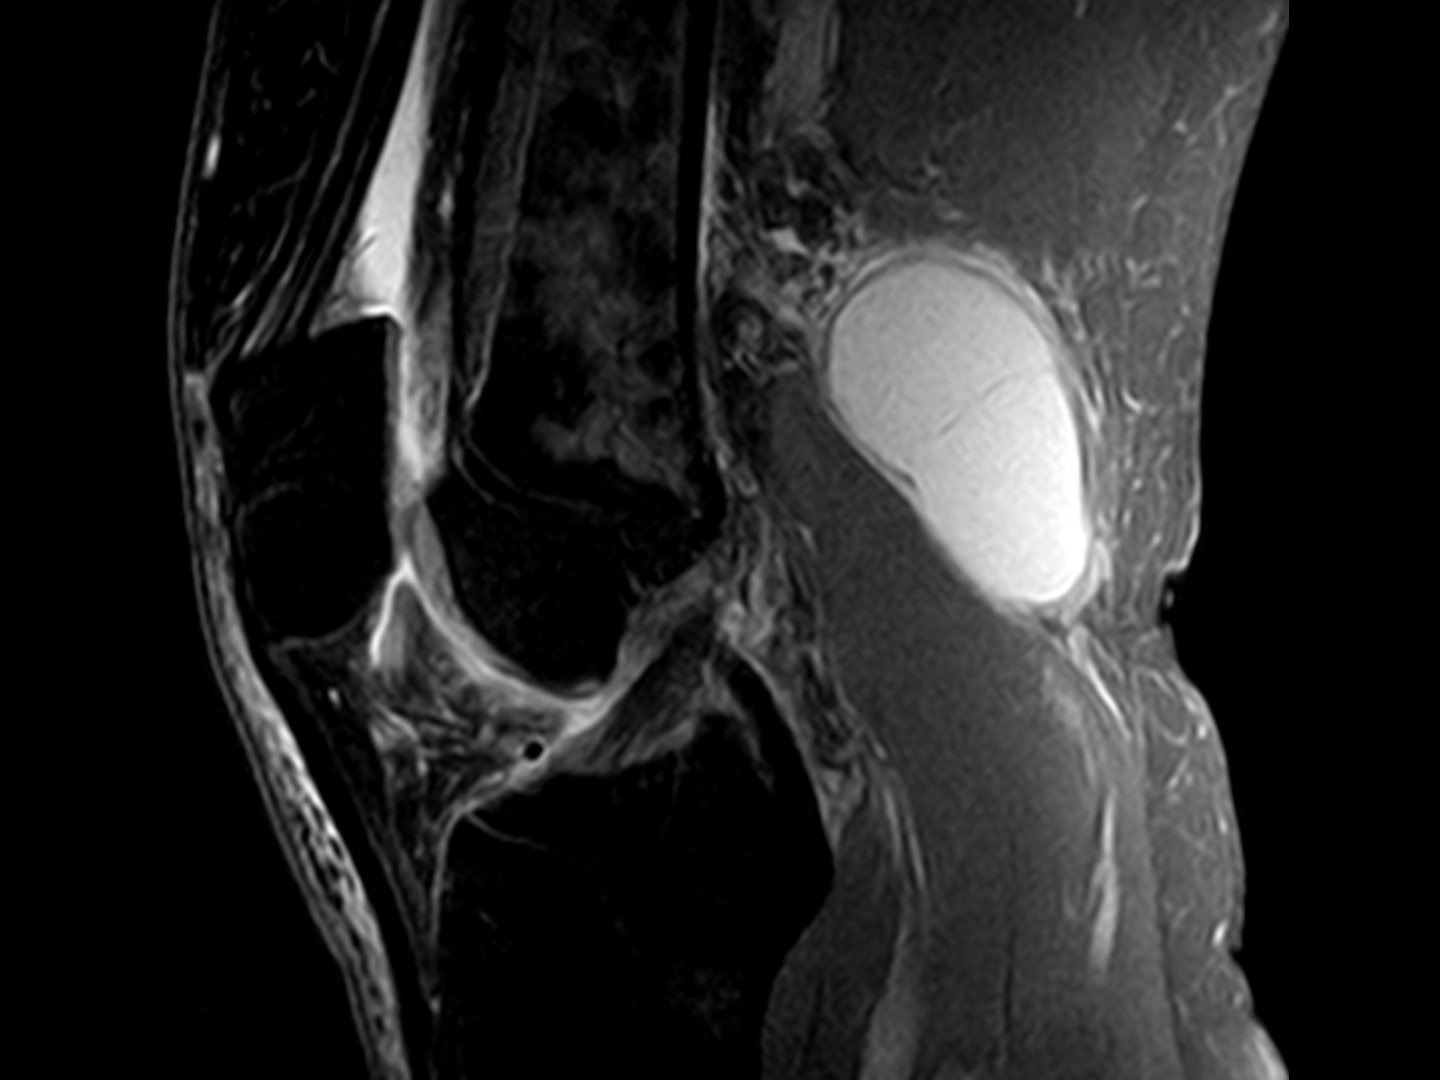

Synovialitis mit unspezifischen Entzündungsinfiltraten

Kniegelenk mit roter Synovialis

Zu Beginn kommt es zur Synovialitis, also einer Entzündung der Gelenkhaut, mit unspezifischen Entzündungsinfiltraten.

Knorpel- & Knochendestruktion

Kaputter Knochen im Kniegelenk

Später kommt es zum entzündlichen Gelenkerguss mit Knorpel- und Knochendestruktion. Teils bilden sich Rheumaknoten.